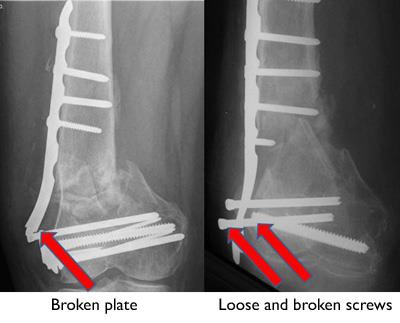

Bone Healing Problems

In some cases, bone healing can be slow (delayed union) or not happen at all (nonunion). If a follow-up X-ray shows rods, plates, and screws breaking or pulling out of the bone, it may be a sign that the bone is not healing. This can happen even if your fracture has been fixed well and you have followed your doctor's guidelines.

Open fractures and high-energy fractures are most at risk of not healing. These challenging fractures are also most at risk for infection, and infection can cause bone healing problems.

To help the fracture heal, your doctor may suggest applying a bone graft to the fracture, and changing or adding to how it was fixed (plates, screws, rods).

Broken plate and screws in a poorly healing distal femur fracture

In many cases, the devices used to fix a fracture break or loosen when the fracture fails to heal.